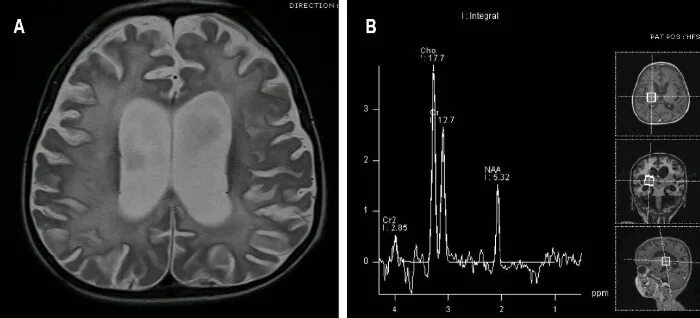

Подострый склерозирующий панэнцефалит